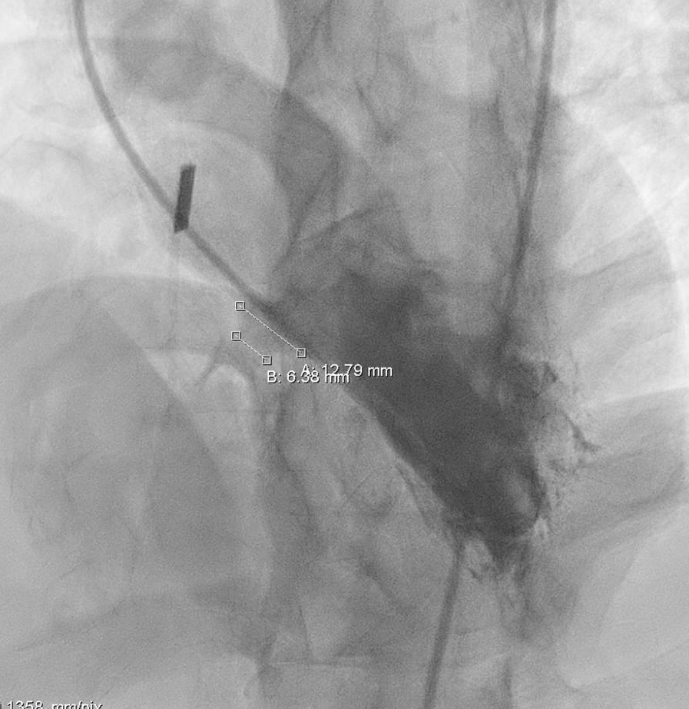

术中造影

结合实际术中造影,为大型膜部瘤室间隔缺损,左室入口直径12.79mm,右室出口直径为6.38mm,选择腰部直径为14的全降解封堵器进行封堵。